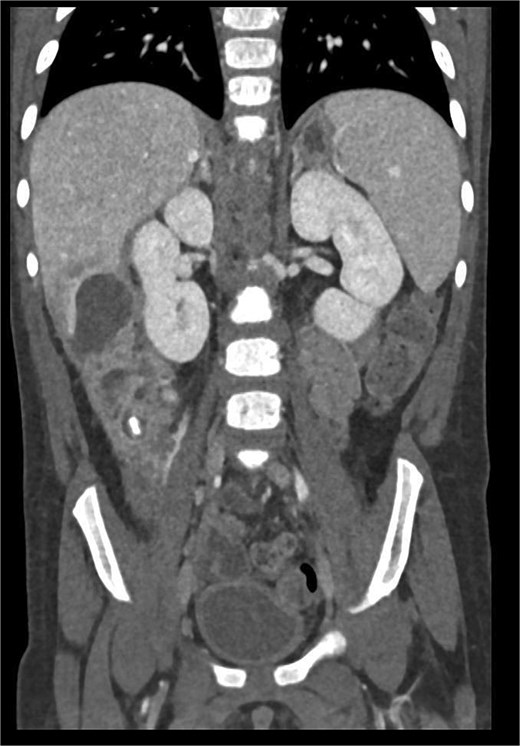

Imaging plays a crucial role in diagnosing appendicitis and its complications. Ultrasound is often the initial modality used, but it may have limited sensitivity in detecting intra-abdominal abscesses, particularly when the appendix is not visualized or when findings are inconclusive [4, 5]. In such cases, contrast-enhanced CT is considered the gold standard, providing detailed visualization of the appendix and associated complications, including abscess formation [2, 4]. In the present case, the initial ultrasound findings suggested an atypical position of the appendix and a pathological fluid collection, but CT imaging confirmed a retrocecal appendix and subhepatic abscesses (Figs 4 and 5), guiding appropriate management.

CT axial view of a subhepatic abscess. Contrast-enhanced capsule and fluid-air level visible.